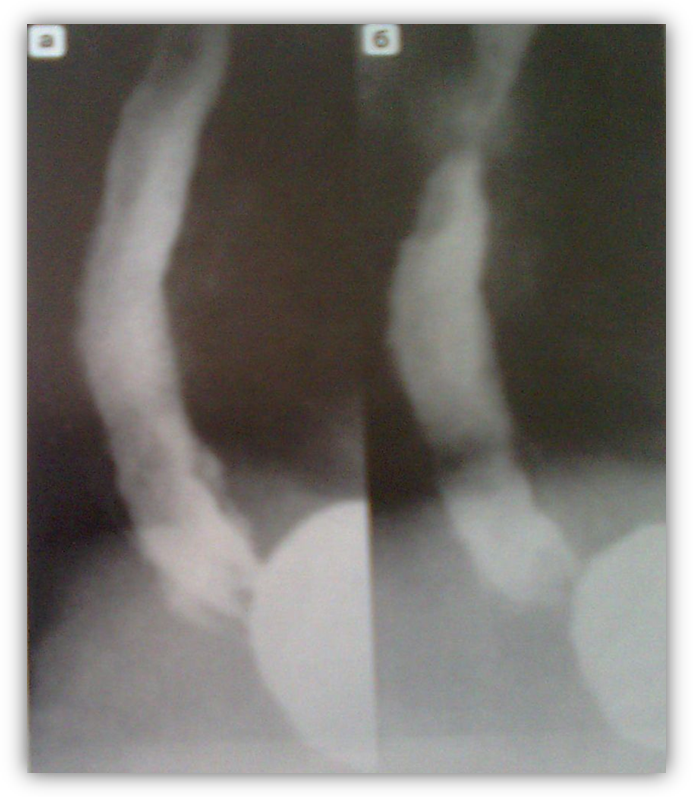

9. Рентгенограма стравоходу

Зображує варикозне розширення вен стравоходу: стравохід трохи розширений. Рельєф внутрішньої поверхні представлений подушкоподібними підвищеннями. На контурах стравоходу ці утворення створюють картину крайових дефектів наповнення. Стінки стравоходу еластичні. Перистальтика збережена.